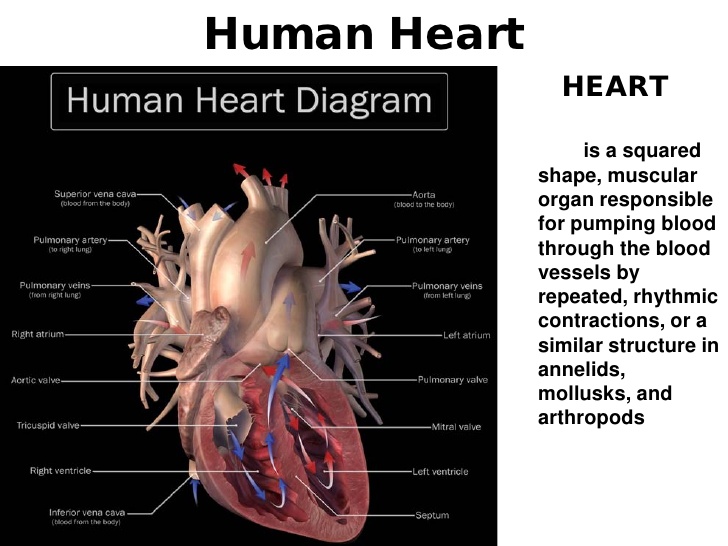

- The heart (structure and function)